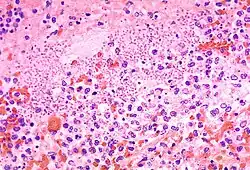

Histologischer Schnitt einer Lunge, Lungenpest

Histologischer Schnitt glatter Muskulatur (HE)